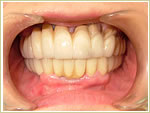

症例1 32歳 男性 画像拡大

治療前 治療後